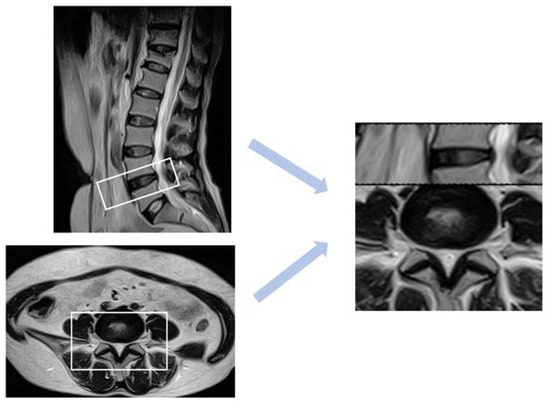

In brief, the logic flow of the proposed two-stage classification process is shown in Figure 2. In this study, we initially employed the Mask RCNN model to localize and classify the lumbar spine’s intervertebral discs and vertebrae in sagittal spine images. Although we used masks parallel to the image to cover the regions of interest, misalignment between the masks and the actual regions of interest could potentially affect the classification results. However, by using the center points of the bounding boxes as the locational references, the deviations were kept within acceptable limits.

Ref. [40] focused on the morphological analysis and feature recognition of the herniated intervertebral disc during the classification and geometric diagnosis of intervertebral disc herniation (HIVD). It shows that the diagnosis of degenerative disc disease is inseparable from the discrimination of disc herniation. In order to ensure that the model is not disturbed by unnecessary features, the features are located in the area of the intervertebral disc protrusion. According to [41], disc diseases are mainly characterized by the circumference in the axial section. For example, bulging is defined as asymmetric if it is more evident in one section of the periphery of the disc but is not so focal as to be characterized as a protrusion. In our dataset, it can be found that the intervertebral disc protrusion is primarily located in the middle of the lower portion of the axial section image. Based on this, we suppose the height of the axial image is h and the width is w, and take ( 9 / 14 × h , 1 / 2 × w ) as the center point and intercept a rectangular box with a height and width ratio of 1:1.5. Suppose the height of the sagittal image is H and the width is W. Take the key point as the center and divide it according to the ratio of height to width of 1:3. The width is 50 / 512 × W and the height is 150 / 512 × H . The axial image and the sagittal slice at the interception are spliced up and down, and the width and height are unified to 224 × 224 to obtain a multi-angle view of the disc. Figure 7 shows the splicing process of the multi-angle view of the disc.

Figure 3. The example types of images in the dataset provided by Tianchi competition. (Left) T2-weighted sagittal image. (Middle) T2-weighted axial image. (Right) T1-weighted sagittal image. T1-weighted images are produced by using short TE and TR times, while T2-weighted images are produced by using longer TE and TR times.